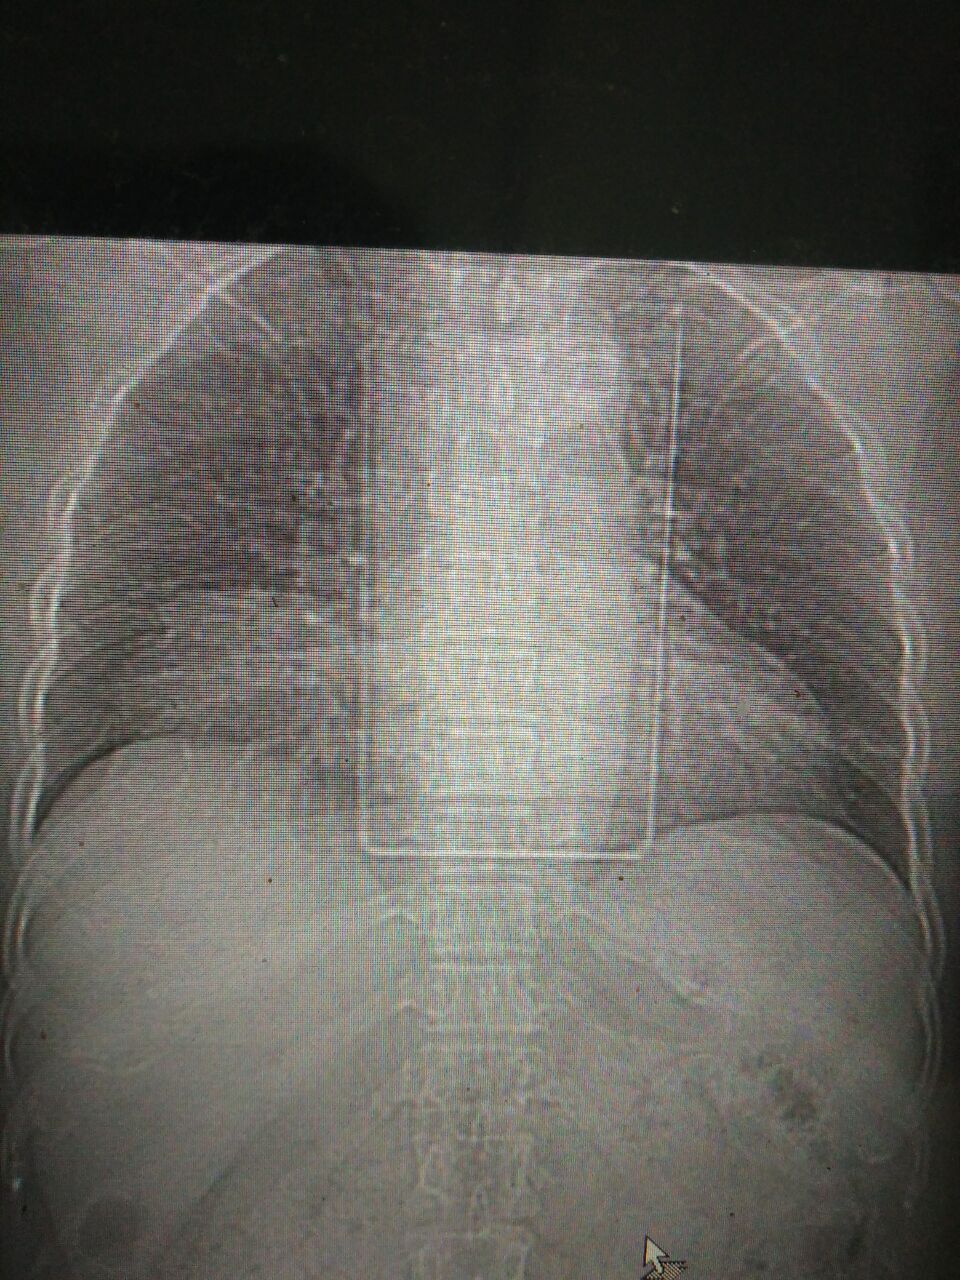

CT52678:女48岁,腹部疼痛就诊

】女48岁,腹部疼痛就诊

右心隔角区脂肪瘤

图像太少;有没有可能是胸骨旁裂孔疝。